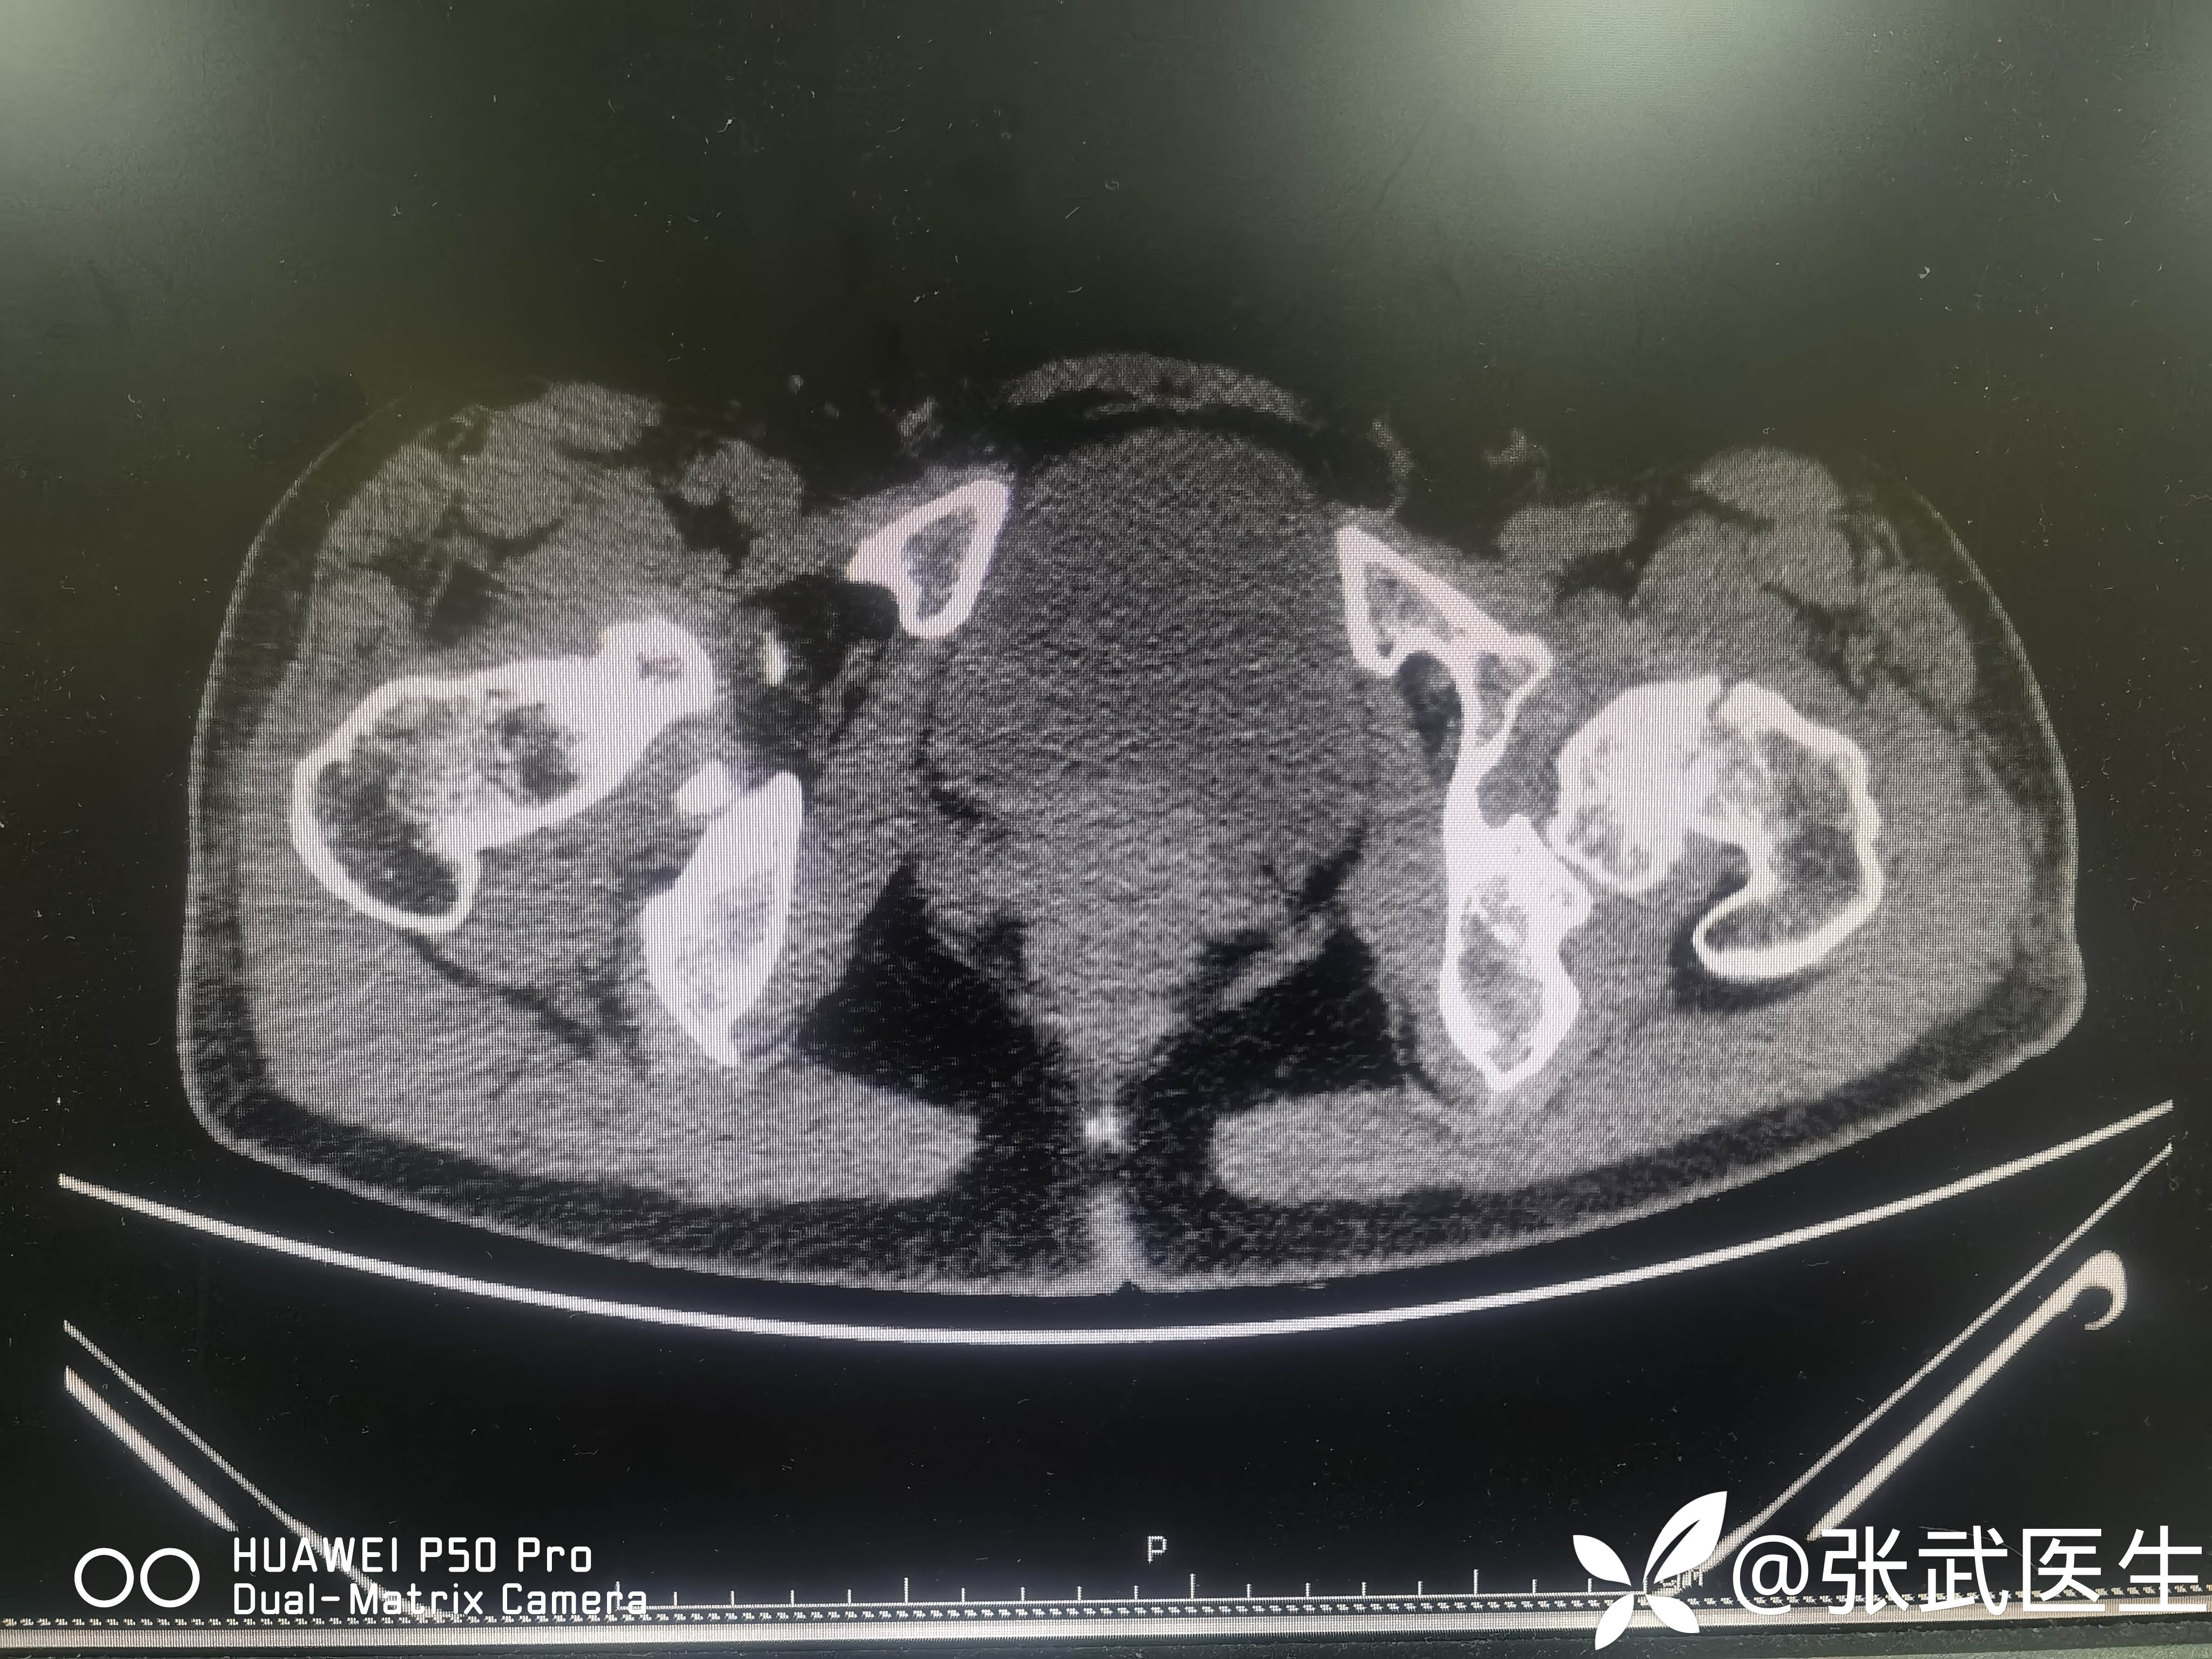

诊断:左股骨颈骨折 Garden II型

术前:

pauwels>50度